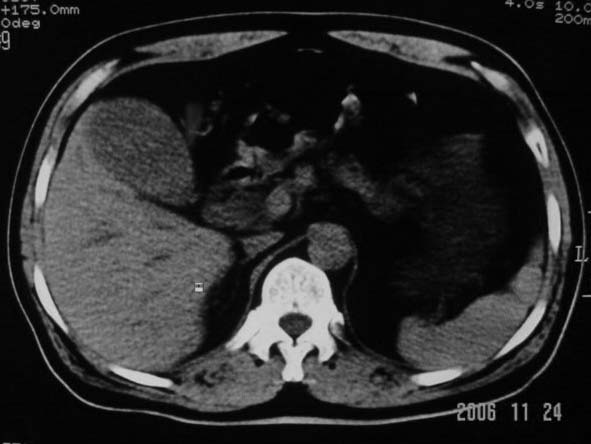

劳烦各位老师看一下最后一幅箭头指的地方是不是胆总管结石.ct值约63hu.

胆总管内结节状高密度灶,边缘隐约可见低密度环绕,首先考虑结石伴肝内胆管扩张; 2、胆囊增大,胆囊炎

不过最好与超声结合或增强扫描

胆总管下端结石

考虑胆总管结石致肝内外胆管扩张,胆囊增大,不像是肿瘤

支持胆总管下段结石并肝内外胆管扩张。

是结石伴梗阻.

楼主的箭头标的太棒了,不看最后一副图,我都没看到胆管下端有问题,象结石